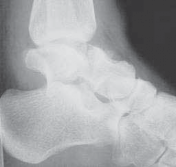

The type I fracture is nondisplaced. Disruption of blood flow is limited to the anterolateral region of the bone. I recommend a computed tomography (CT) scan to confirm no displacement of the fracture before diagnosing a type I fracture. Historically, Hawkins reported a 13% incidence of osteonecrosis in type I injuries ( FIG 1A).

In the type II talar neck fracture there is displacement of the talar dome fragment, which is routinely posterior, often depicting clear subluxation of the talar body. Blood flow to the medial body and head is preserved. The type II talar neck fracture has a 20% to 50% risk of avascular necrosis ( FIG 1B). 697

FIG 1 • Hawkins classification of talar fractures. A. Type I: disruption of anterolateral perfusion. B. Type II: medial perfusion intact. C. Type III: all D sources of blood flow injured. D. Type IV: dislocation of all articulations. 1. In the type III injury, the transverse fracture of the talar neck is associated with dislocation of the talar body. The incidence of osteonecrosis of the talar body is 50% to 100%. All major perfusion to the body of the talus is damaged ( FIG 1C). 2. A type IV injury of the talar neck has been documented; it is a type III fracture-dislocation with associated talonavicular dislocation.2 All extraosseous blood flow to the talus is considered disrupted. The value of the Hawkins classification is that it allows the orthopedic surgeon to predict what to expect with a specific talar neck injury. Open reduction and rigid internal fixation is the recommended treatment ( FIG 1D). 1. Talar body fractures are defined as fractures extending into or posterior to the lateral process. PATIENT HISTORY AND PHYSICAL FINDINGS 2. Fractures of the talus are commonly associated with vehicular trauma and falls. 1. The relationship of severe lower extremity trauma and airbags is well known. After airbag deployment, the torso and lower extremities are directed toward the floor panel of the car. 2. I believe that the incidence of high-energy hindfoot trauma will increase over time. Globally, transport related injuries remain the leading cause of disability from injury. By 2020, traffic injuries will increase from a current 9th position to 3rd disability-adjusted life years lost. 3. The history and the clinical status of the talar injury must be carefully recorded because the injury severity is likely to correlate with the long-term patient outcome. 1. On the initial examination the physician should note pain, motion, crepitus, deformity, soft tissue swelling, open fractures, and associated fractures of adjacent bones to the foot and ankle and should perform a complete neurovascular evaluation of the extremity. 4. Detailed documentation of the talus fracture pattern and local soft tissue injury is paramount. 1. Soft tissue local pressure phenomenon, commonly found anterolaterally in closed type III fractures of the talar neck, may precipitate full-thickness pressure necrosis of the skin if not decompressed early. 2. Severe swelling of the ankle is common in the acute fracture of the talus and may progress to fracture blister formation, precluding safe execution of operative incisions. 5. The physician should examine the skin for swelling, ecchy-mosis, fracture blisters, and deformity; these are signs of a closed fracture. 1. A closed injury with mild or moderate swelling (bony landmarks palpable) indicates talar neck type I and II fractures and process fractures. 2. A closed injury with severe swelling indicates talar neck type III and IV fractures and body fractures. 6. Open fractures will be apparent by the transverse, medial, or supramalleolar traumatic laceration of the ankle. Lateral, posterior, and plantar wounds are uncommon. 7. The physician should perform vascular, neurosensory, and myotendinous examinations of the foot and ankle. IMAGING AND OTHER DIAGNOSTIC STUDIES 8. Three plain radiographic views are necessary to radiographi-cally evaluate talus fractures: anteroposterior (AP), mortise (15-degree internal rotation view), and lateral images of the ankle. 1. The AP and mortise views of the ankle demonstrate alignment of the talar body in the ankle mortise. The lateral view depicts the sagittal outline of the talus. 9. The Canale view is used to assess varus or valgus malalignment of the talar neck, particularly with Hawkins type I and II injuries. The knee must be flexed and the foot in equinus and everted, with the x-ray tube directed 15 degrees caudad ( FIG 2A).